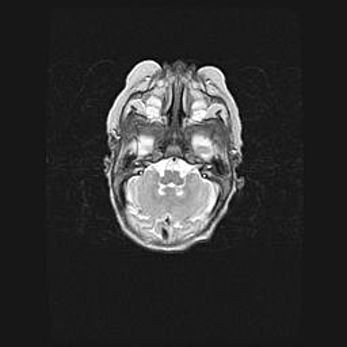

Церебральная ишемия II.

Возраст: 5 дней

Вес: 3400 г

Пол: женский

Окружность головы: 35 см

Срок гестации: 39 недель

Церебральная ишемия – это заболевание, характеризующееся недостаточностью (гипоксией) либо полным прекращением (аноксией) снабжения мозга кислородом по причине закупорки одного или нескольких сосудов. Это приводит к  что метаболическим расстройствам различной степени тяжести в тканях головного мозга, развитию коагуляционных некрозов и гибели нейронов.